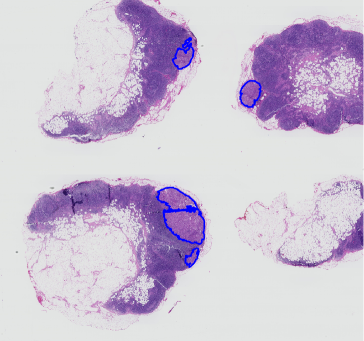

In Figure 3 (4), we report some examples of the 646464 attention filters for each of the two sets of attention maps that were generated by FT-R34-AC (PT-R34-AC) for two different WSIs with tumors, for dataset Camelyon 16 (TUPAC16). The filters of the set of the max pooling-based attention maps (AMp𝐴𝑀𝑝AMp) highlight specific features on critical regions, while the filters of the set of the min pooling-based attention maps (Amp𝐴𝑚𝑝Amp) compute a complementary attention inducing a more effective feature learning. Indeed, it can be noted from Figures 3 and  4 that Amp𝐴𝑚𝑝Amp provides a lower but more diffused response, so leading the model to consider a higher number of patches but with a lower confidence degree.

Refer to caption

Figure 4: Examples of some attention maps for TUPAC16